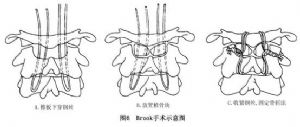

14.3.2 Brook手术

Brook手术多用于单纯性寰枢不稳者,因勿需对寰椎进行复位,因此可将钢丝穿过植骨片,并使之与枢椎靠拢(植骨块下方中央有一缺口,可骑至枢椎棘突上),收紧钢丝即达固定融合的目的,尤其适合于年幼的患者(图6,7)。其具体操作如下:

①准备植骨床:即将寰椎后弓及枢椎椎板分别加以暴露,并除去骨外的软组织。

②准备骨块:从髂骨(或义骨)切取2块1.25cm×3.5cm左右的长方形骨块(视个体而决定骨块的大小)。

③穿过钢丝:一般用双股18号钢丝穿过寰椎后弓和枢椎椎板,也可选用带固定扣的钛丝(缆),不仅柔软、安全,且其固定强度高,抗疲劳性强。

④结扎骨块:将备用的骨块修剪后,置于寰枢椎之间(两侧),并将其打结扎紧。在此过程中应防止颈椎过度仰伸及寰枢椎之间的移位,除非需要借此复位者。